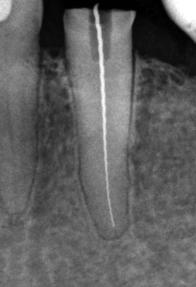

Längenvermessung eines Wurzelkanals